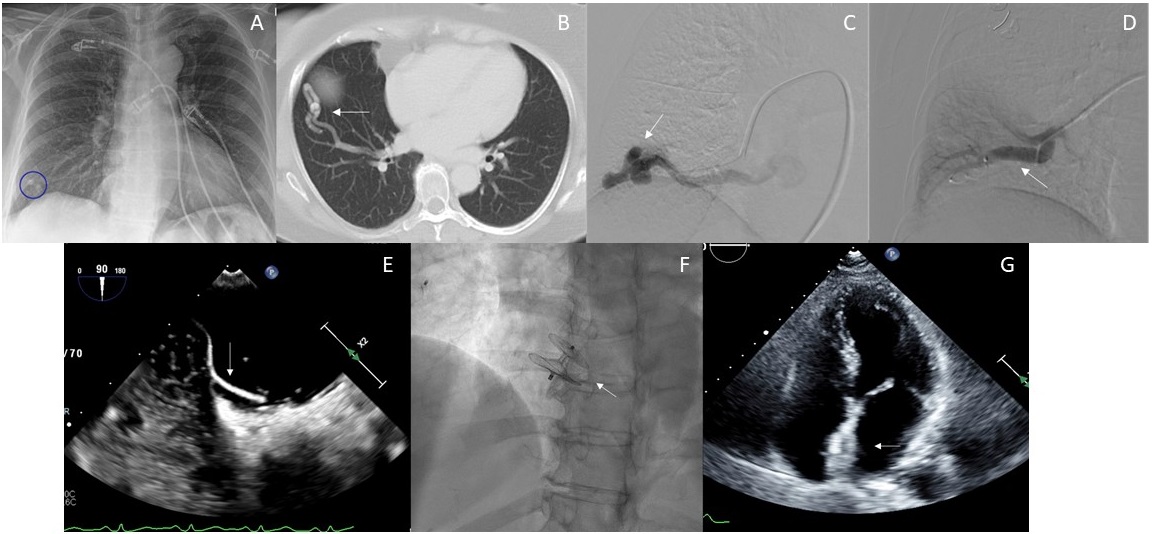

A 64-year-old woman presented with acute onset left-sided facial droop, left upper extremity paresis, and aphasia. Magnetic resonance imaging demonstrated acute infarction of the right thalamus. A chest x-ray revealed a 1.7-cm nodular opacity at the right lung base (Figure A). A contrast-enhanced computed tomography (CT) revealed a right lower lobe (RLL) pulmonary arteriovenous malformation (AVM) (Figure B), and a transthoracic echocardiogram (TTE) with agitated saline showed bubbles in the left atrium.

The patient underwent pulmonary angiography, which demonstrated a simple AVM arising from a branch of the RLL pulmonary artery (Figure C), with subsequent embolization. Via a 10F femoral venous sheath, the pulmonary arterial system was catheterized using a 7F guide catheter and 4F Glidecath (Terumo). A 12-mm Amplatzer AVP II plug (Abbott) was inserted for embolization (Figure D). Repeat TTE continued to show bubbles in the left atrium. A transesophageal echocardiogram revealed a patent foramen ovale (PFO) with atrial septal aneurysm (Figure E). The patient was referred for concomitant PFO closure. A 6F multipurpose guide catheter was advanced across the PFO into the pulmonary vein. An 8F Amplatzer intravascular delivery system was subsequently advanced across the inter-atrial septum over a stiff wire, and a 30-mm Amplatzer PFO Occluder (Abbott) was deployed and released (Figure F) utilizing intracardiac echocardiography guidance. Repeat TTE (Figure G) and CT demonstrated the absence of bubbles in the left atrium and complete occlusion of the pulmonary AVM, respectively.